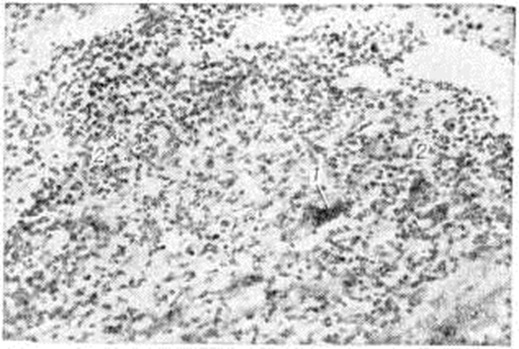

Рис. 1.

Микропрепараты миокарда животного при экспериментальном миокардите: а — очаговый кардиомиоцитолиз; стрелками указаны кардиомиоциты, подвергшиеся лизису; окраска железным гематоксилином по Гейденгайну, × 125; б — лимфогиетиоцитарный инфильтрат в интерстиции и отёк (указан стрелками); окраска гематоксилин-эозином, × 312.

При экспериментальном Миокардит установлены нарушения окислительно-восстановительных и энергетических процессов в миокарде. Метаболические нарушения сопровождаются очаговыми и диффузными морфологический реакциями, которые дают возможность выделить паренхиматозный, воспалительно-инфильтративный, некротический, гигантоклеточный и смешанный варианты экспериментального Миокардит Наряду с очаговым кардиомиоцитолизом (рисунок 1, а), отёком и лимфогистиоцитарными инфильтратами в интерстиции (рисунок 1, б) наблюдается выраженная реакция антиген—антитело и с помощью меток выявляются В-лимфоциты и фиксированные антитела. Подострый и хронический варианты экспериментального Миокардит морфологически характеризуются мозаичностью и сочетанием воспалительных изменений с атрофией, гипертрофией и склерозом в миокарде. В эксперименте показана обратимость острого и подострого вариантов Миокардит, особенно под влиянием экспериментальной фармакотерапии. На моделях экспериментального Миокардит апробирован ряд средств, оказавшихся эффективными для лечения Миокардит у людей: противовирусные препараты (интерферон, кутизон, ремантадин), антибиотики, вакцины и сыворотки (противодифтерийная, противоменингококковая, противогриппозная), иммуно депрессоры (имуран), ненаркотические анальгетики (бруфен, индометацин), гипосенсибилизирующие и противовоспалительные препараты, анаболические средства.